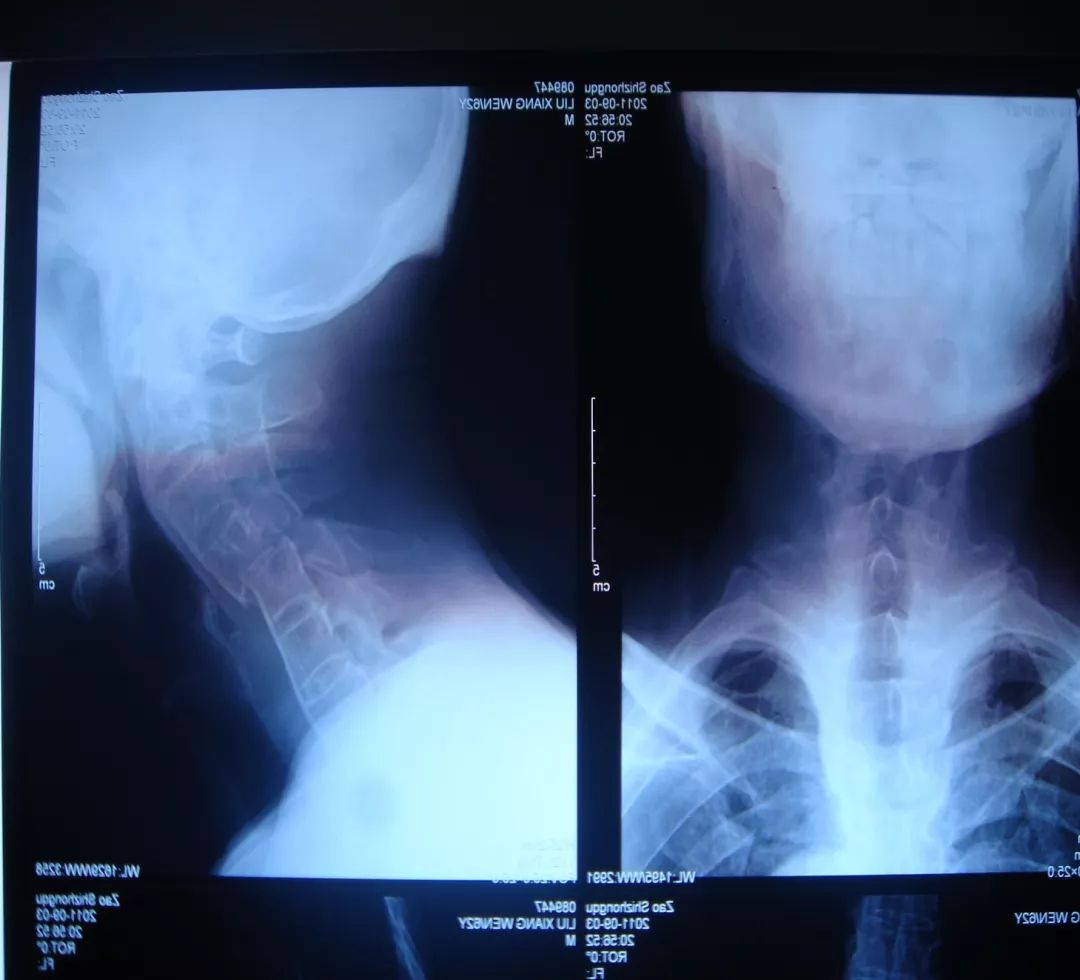

患者,男性,75岁,因外伤致颈部疼痛伴活动受限7天入院。患者入院前在当地医院确诊为:枢椎齿状突骨折Anderson-D’Alonzo分型Ⅱ型。

对于本患者来说,齿状突骨折后导致寰枢椎不稳,极易引起延髓或椎动脉损伤,严重者当场死亡。但患者同时合并严重胸腰椎后凸畸形,颈部后伸受限,不具备前路手术条件,这就给其治疗更增加了额外的困难。而由于手术部位延髓及椎动脉等血管神经密布,手术难度高、风险极大,稍有不慎,患者就会有生命危险。而患者家属在了解到手术的危险性后,曾自行到上级医院咨询专家,上级医院专家考虑围手术期死亡的风险,对于本例患者亦不愿提供手术治疗的机会。

经过全程监护和系统治疗,患者术后恢复良好,骨折解剖复位,复查X线及CT显示固定位置佳,术后3天下地行走,术后4天即出院回家休养。